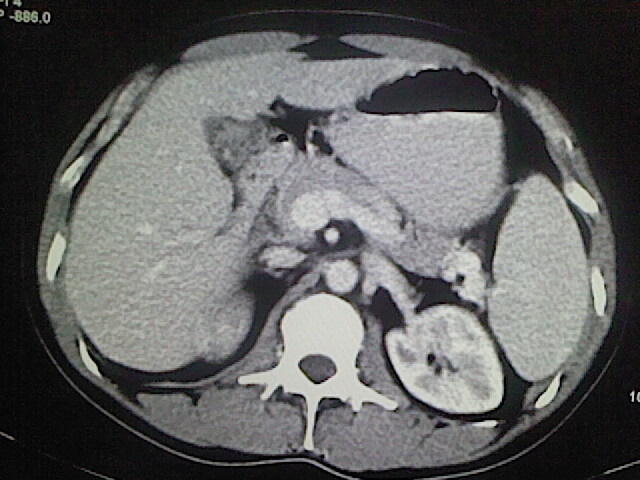

以下是引用卜一在2009-3-14 9:49:00的发言:[br]胆囊萎缩,胆囊壁不规则增厚,内部结构模糊,增强明显强化。另:肝左叶外侧段肝囊肿。支持:慢性胆囊炎!高度可疑:胆囊癌!

以下是引用余辉在2009-3-14 8:48:00的发言:[br]1)慢性胆囊炎。2)肝左叶外侧段肝囊肿。3)脂肪肝。[br]支持,胆囊萎缩,密度增高,不知b超具体有何提示,钙胆汁?结石?

以下是引用jiangjing在2009-3-14 10:18:00的发言:[br]1)慢性胆囊炎。2)肝左叶外侧段肝囊肿。3)脂肪肝。4.】建议行肝功能检查